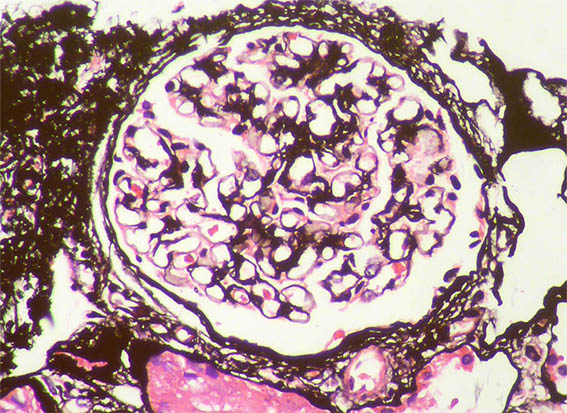

Figura 8. Plata-metenamina, X200.